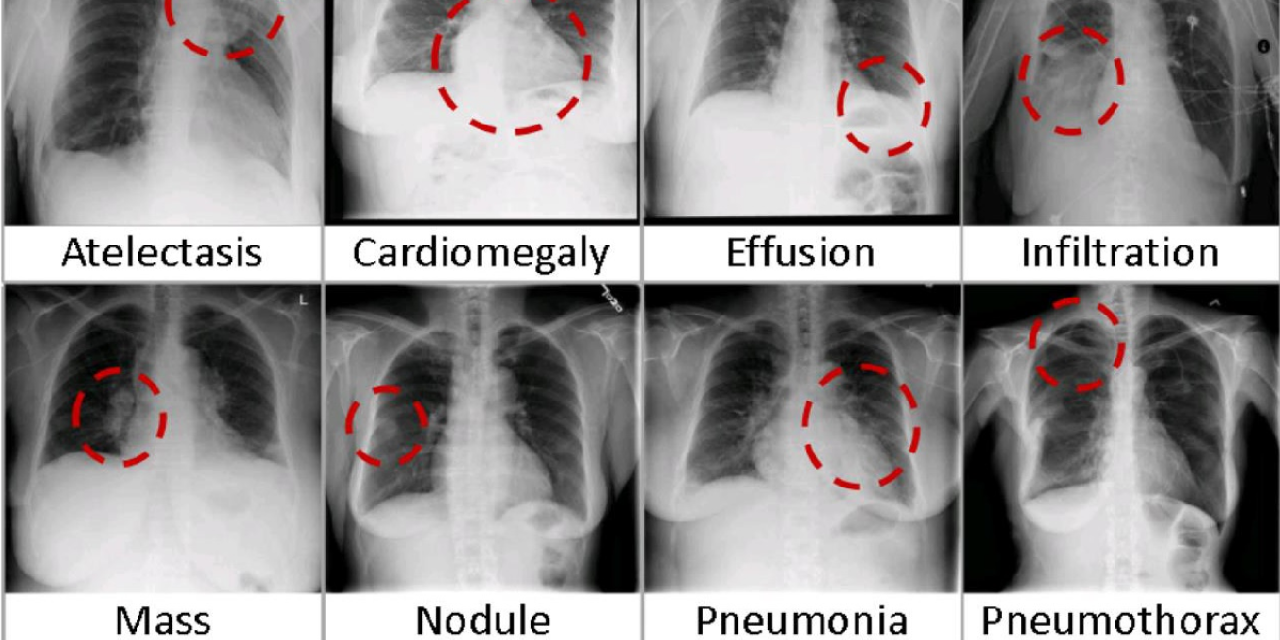

1. Image Classification

Image classification is the process of assigning a label to an entire image based on its visual content. This application is foundational in computer vision and serves as the basis for more complex tasks.

• Healthcare:

Image classification is used in medical imaging to identify diseases and abnormalities in X-rays, MRIs, and CT scans. For instance, algorithms can classify images of skin lesions to detect melanoma.

blog image